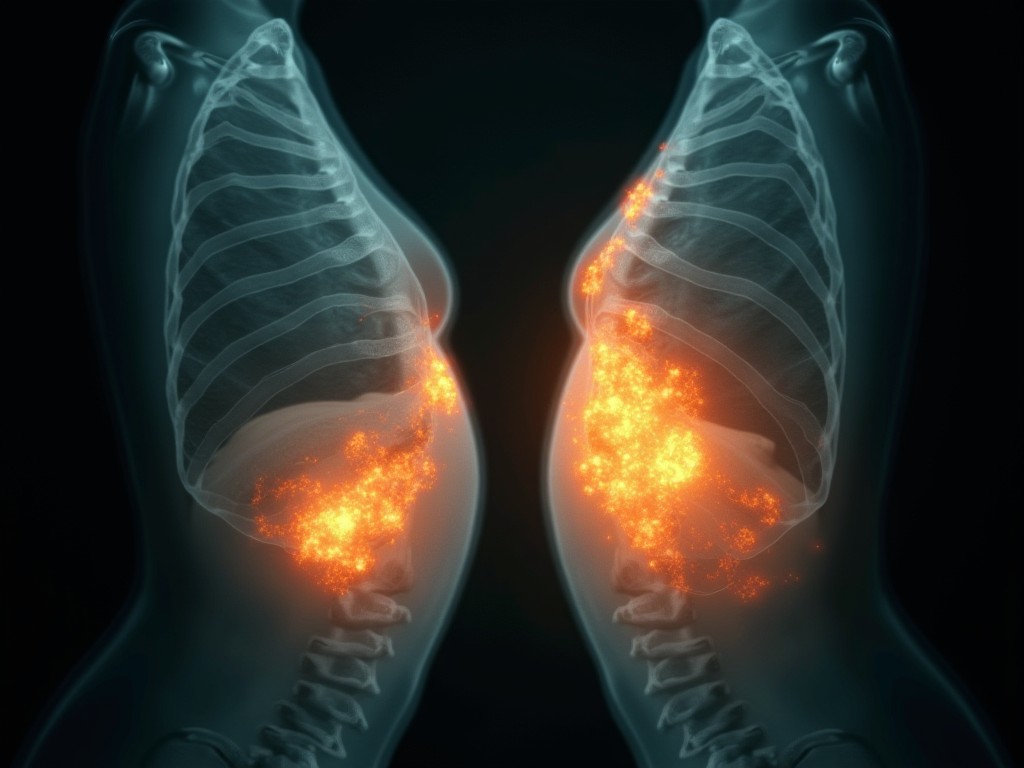

Hình dung một cảnh tượng: chị em đi khám vú định kỳ, ảnh chụp X-quang được gửi đi phân tích — và không chỉ phát hiện ung thư vú, mà còn cảnh báo sớm về nguy cơ bệnh tim. Đó không phải là tưởng tượng nữa. Một nghiên cứu mới từ Đại học Emory (Mỹ) vừa công bố trong tạp chí European Heart Journal cho thấy, công nghệ trí tuệ nhân tạo (AI) có thể làm được điều này.

Bác sĩ Hari Trivedi, người dẫn dắt nghiên cứu, chia sẻ rằng bệnh tim là nguyên nhân tử vong hàng đầu ở phụ nữ trên toàn thế giới. Tuy nhiên, phụ nữ thường bị chẩn đoán và điều trị chậm hơn nam giới. Điều thú vị là: ảnh chụp vú thường quy có thể tiết lộ tích tụ canxi trong các động mạch vùng ngực — một dấu hiệu cảnh báo về sức khỏe tim mạch.

Thay vì yêu cầu phụ nữ thêm một xét nghiệm khác, đội nghiên cứu quyết định dùng AI để phân tích những ảnh chụp vú mà họ đã có. "Chúng tôi muốn kiểm tra xem liệu AI có thể xác định phụ nữ có nguy cơ bệnh tim mạch mà không cần chi phí hay sự bất tiện thêm nào," bác sĩ Trivedi giải thích.

Nghiên cứu này bao gồm hơn 123.000 phụ nữ đã tham gia khám sàng lọc ung thư vú, nhưng chưa có bệnh tim mạch. Các nhà khoa học sử dụng AI để phân tích mức độ tích tụ canxi trong động mạch vú.